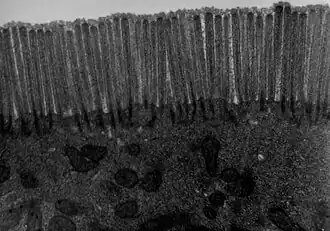

Transmission electron microscope (TEM) image of human jejunum

The interior surface of the jejunum—which is exposed to ingested food—is covered in finger–like projections of mucosa, called villi, which increase the surface area of tissue available to absorb nutrients from ingested foodstuffs. The epithelial cells which line these villi have microvilli. The transport of nutrients across epithelial cells through the jejunum and ileum includes the passive transport of sugar fructose and the active transport of amino acids, small peptides, vitamins, and most glucose. The villi in the jejunum are much longer than in the duodenum or ileum.

- The villi of the jejunum look like long, finger-like projections, and are a histologically identifiable structure.